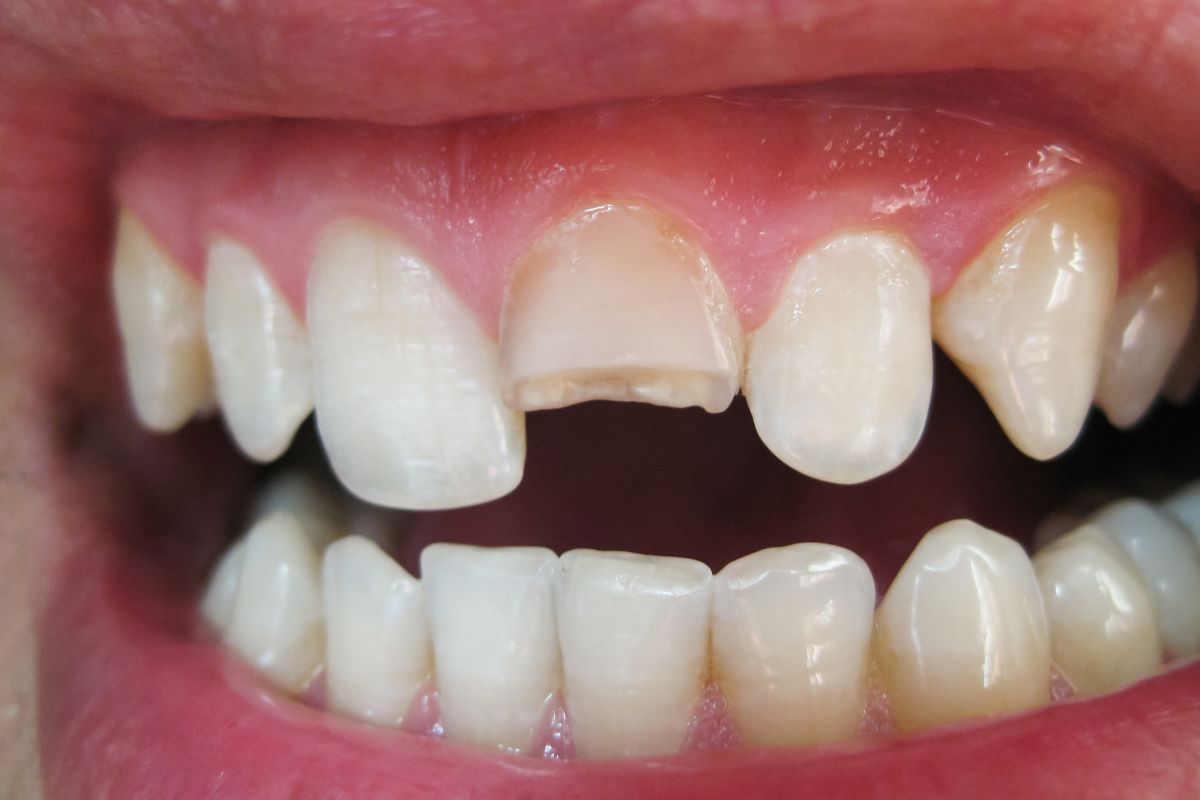

Most people think of bright, perfect smiles when they hear the term cosmetic dentistry. While cosmetic dentists help improve aesthetics, they can also provide restorative services like cavity treatment. At Knoxville Smiles at Malone & Costa Dentistry, we marry form and function to create healthy, beautiful smiles. Cosmetic Dentistry and Cavity Care in Knoxville What Are Cosmetic Fillings? Cosmetic fillings, or composite fillings, address cavities by maintaining the natural look of the teeth. The process involves removing the decayed portion of the tooth, cleaning the affected area, and then filling it with the tooth-colored resin. Unlike traditional metallic fillings, cosmetic … Continue reading